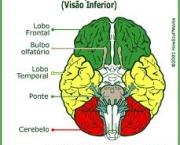

Talvez você nunca tenha parado para pensar nisso, a menos que trabalhe ou estude a área médica. Porém, você já deve ter visto o cérebro na Tv ou em vidros na sala de aula. Esse cérebros, na maioria das vezes são de coloração cinza, amarelada, branca ou verde. Já o cérebro vivo e pulsante que está em seu crânio, não é apenas insosso e frio cinza, também é preto, branco e vermelho. Temos todas as cores do arco-íris no nosso corpo no osso, tecido, na forma sanguínea, e outros líquidos.

Como muitos mitos, este é apenas um pouco verdadeiro, porque muita parte do cérebro é cinza. “O famoso detetive Hercule Poirot, dos livros de mistério da escritura Agatha Christie, diz com frequência que está usando suas ‘pequenas células cinzas’”. A massa cinza existe em cada parte do cérebro como na medula, ela é composta de tipos diferentes de células, como os neurônios, entretanto o cérebro contém também uma massa branca, que contém fibras nervosas conectadas a massa cinza.